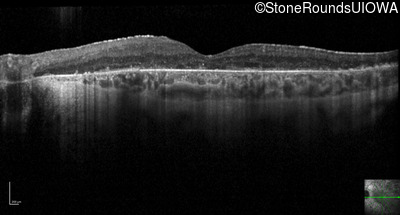

Optical Coherence Tomography - Right - 20/32 -1

Exemplar / OCT Stack

OCT Stack